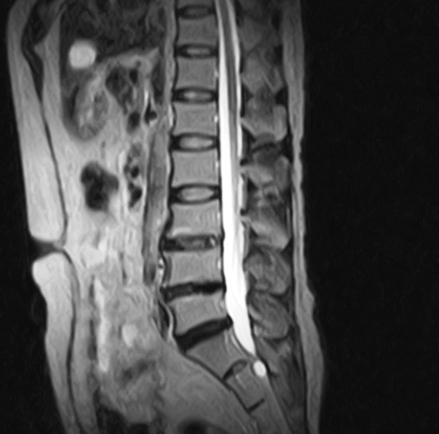

初診時にMRIを見せていただいた時は、L4・L5の椎間板は変性しているものの画像上は手術の対象では無いと感じたが、とにかく痛み痺れが尋常ではなかった為、手術の選択もありでは無いかと思った。

では何故、画像上は大きな問題では無いように見えて、症状が強かったのか?

レントゲンやMRIで正常な椎間板と思われるケースでも、線維輪に亀裂が入っていて、痛みの成分である髄核が少しずつ漏れ出している場合や椎間板周囲組織の炎症によるものではないかと考える。